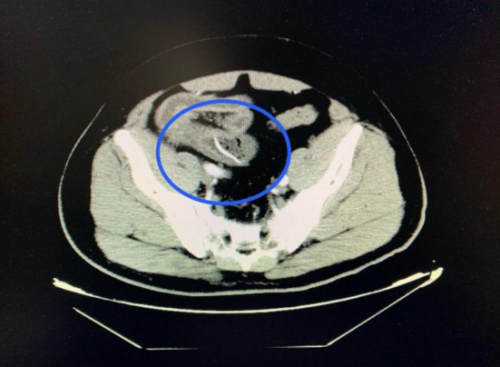

(南华大学附属长沙中心医院)急诊医学科就诊。医生详细询问病情并进行体格检查后,立即安排了腹部 CT 扫描。CT结果显示:回肠高密度影,考虑尖锐异物并小肠穿孔、腹膜炎。结合阳宇军三天前吃甲鱼的经历,医生高度怀疑是误吞甲鱼骨导致了肠穿孔。

CT扫描可见一尖锐的鱼刺状异物